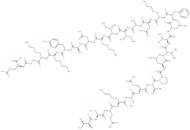

CAS: 77761-27-4 - 6-31-b-Endorphin (sheep),27-L-tyrosine-31-L-glutamic acid-

Fórmula:C131H218N34O40

- b-Endorphin (sheep),1-de-L-tyrosine-2-deglycine-3-deglycine-4-de-L-phenylalanine-5-de-L-methionine-27-L-tyrosine-31-L-glutamicacid-

- Human b-endorphin 6-31

β-Endorphin (6-31) (human)

CAS:77761-27-4

This b-endorphin fragment, in which the C-terminus is preserved, functions as a non-opioid b-endorphin antagonist …

Fórmula:

C131H218N34O40

Peso molecular:

2909.38

β-Endorphin (6-31), human

CAS:77761-27-4

β-Endorphin is an endogenous opioid neuropeptide and opioid receptor agonist that preferentially binds to μ-opioid …

Fórmula:

C131H218N34O40

Peso molecular:

2909.38

Beta-Endorphin (6-31) (human)

CAS:77761-27-4

Beta-endorphin (6-31) is a synthetic opiate that binds to the opioid receptor. This receptor is …

Fórmula:

C131H218N34O40

Peso molecular:

2,909.34 g/mol